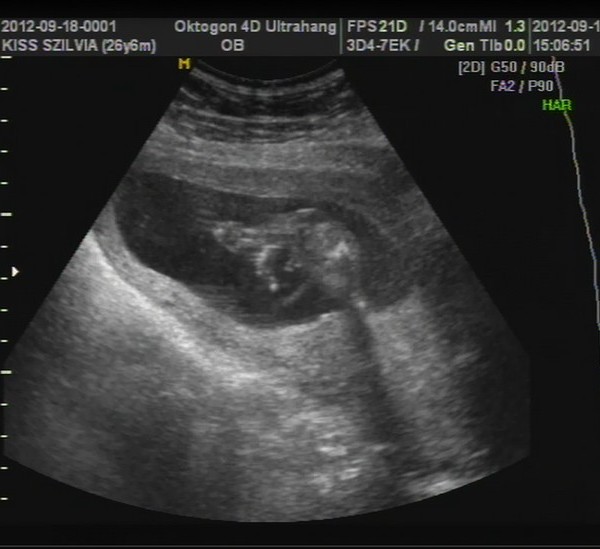

A képek először a babáról. :-) Kép 4d kedvenc :-)

Kép 2d

Kép tappancs

Kép és ott az a pici háromszög a lábikó között a kukac :-)

Sziszianyu de édes ez a baba :D :D :D Hogy bebújt a méhlepénybe:-))) a tappancsos kép is nagyon aranyos:-))))